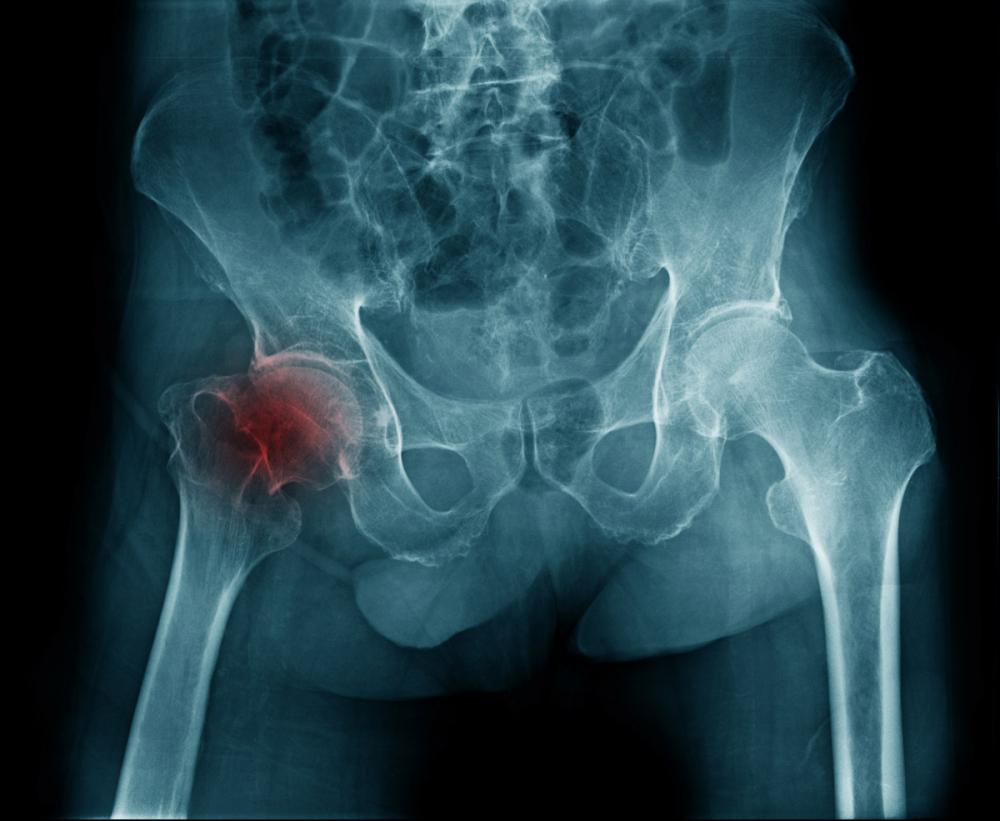

Коксартроз 3 степени тазобедренного сустава

В современном мире артроз считается одним из самых распространенных заболеваний, поражающих суставы. Его возникновение во многом обусловлено малоподвижным образом жизни. Одной из форм артроза является коксартроз. Он развивается в тазобедренном суставе. Коксартроз 3 степени — наиболее тяжелая стадия данного заболевания, которая характеризуется полным истончением хряща, отсутствием синовиальной жидкости и поражением всего сочленения. Как правило, заболевание развивается на фоне патогенных факторов или других недугов. Оно может возникать у представителей всех возрастных групп, однако чаще всего встречается у людей старше 40 лет.

К симптомам коксартроза тазобедренного сустава 3 степени относится постоянная боль, которая не утихает даже в состоянии покоя. Синдром беспокоит даже ночью, в результате чего развивается бессонница. Мышцы ягодиц, бедра и голени атрофируются, а количество суставных движений сокращается. При ходьбе человек вынужден опираться на трость. Если недуг развивается только в одном суставе, то происходит смещение таза, в результате которого длина одной конечности становится меньше.